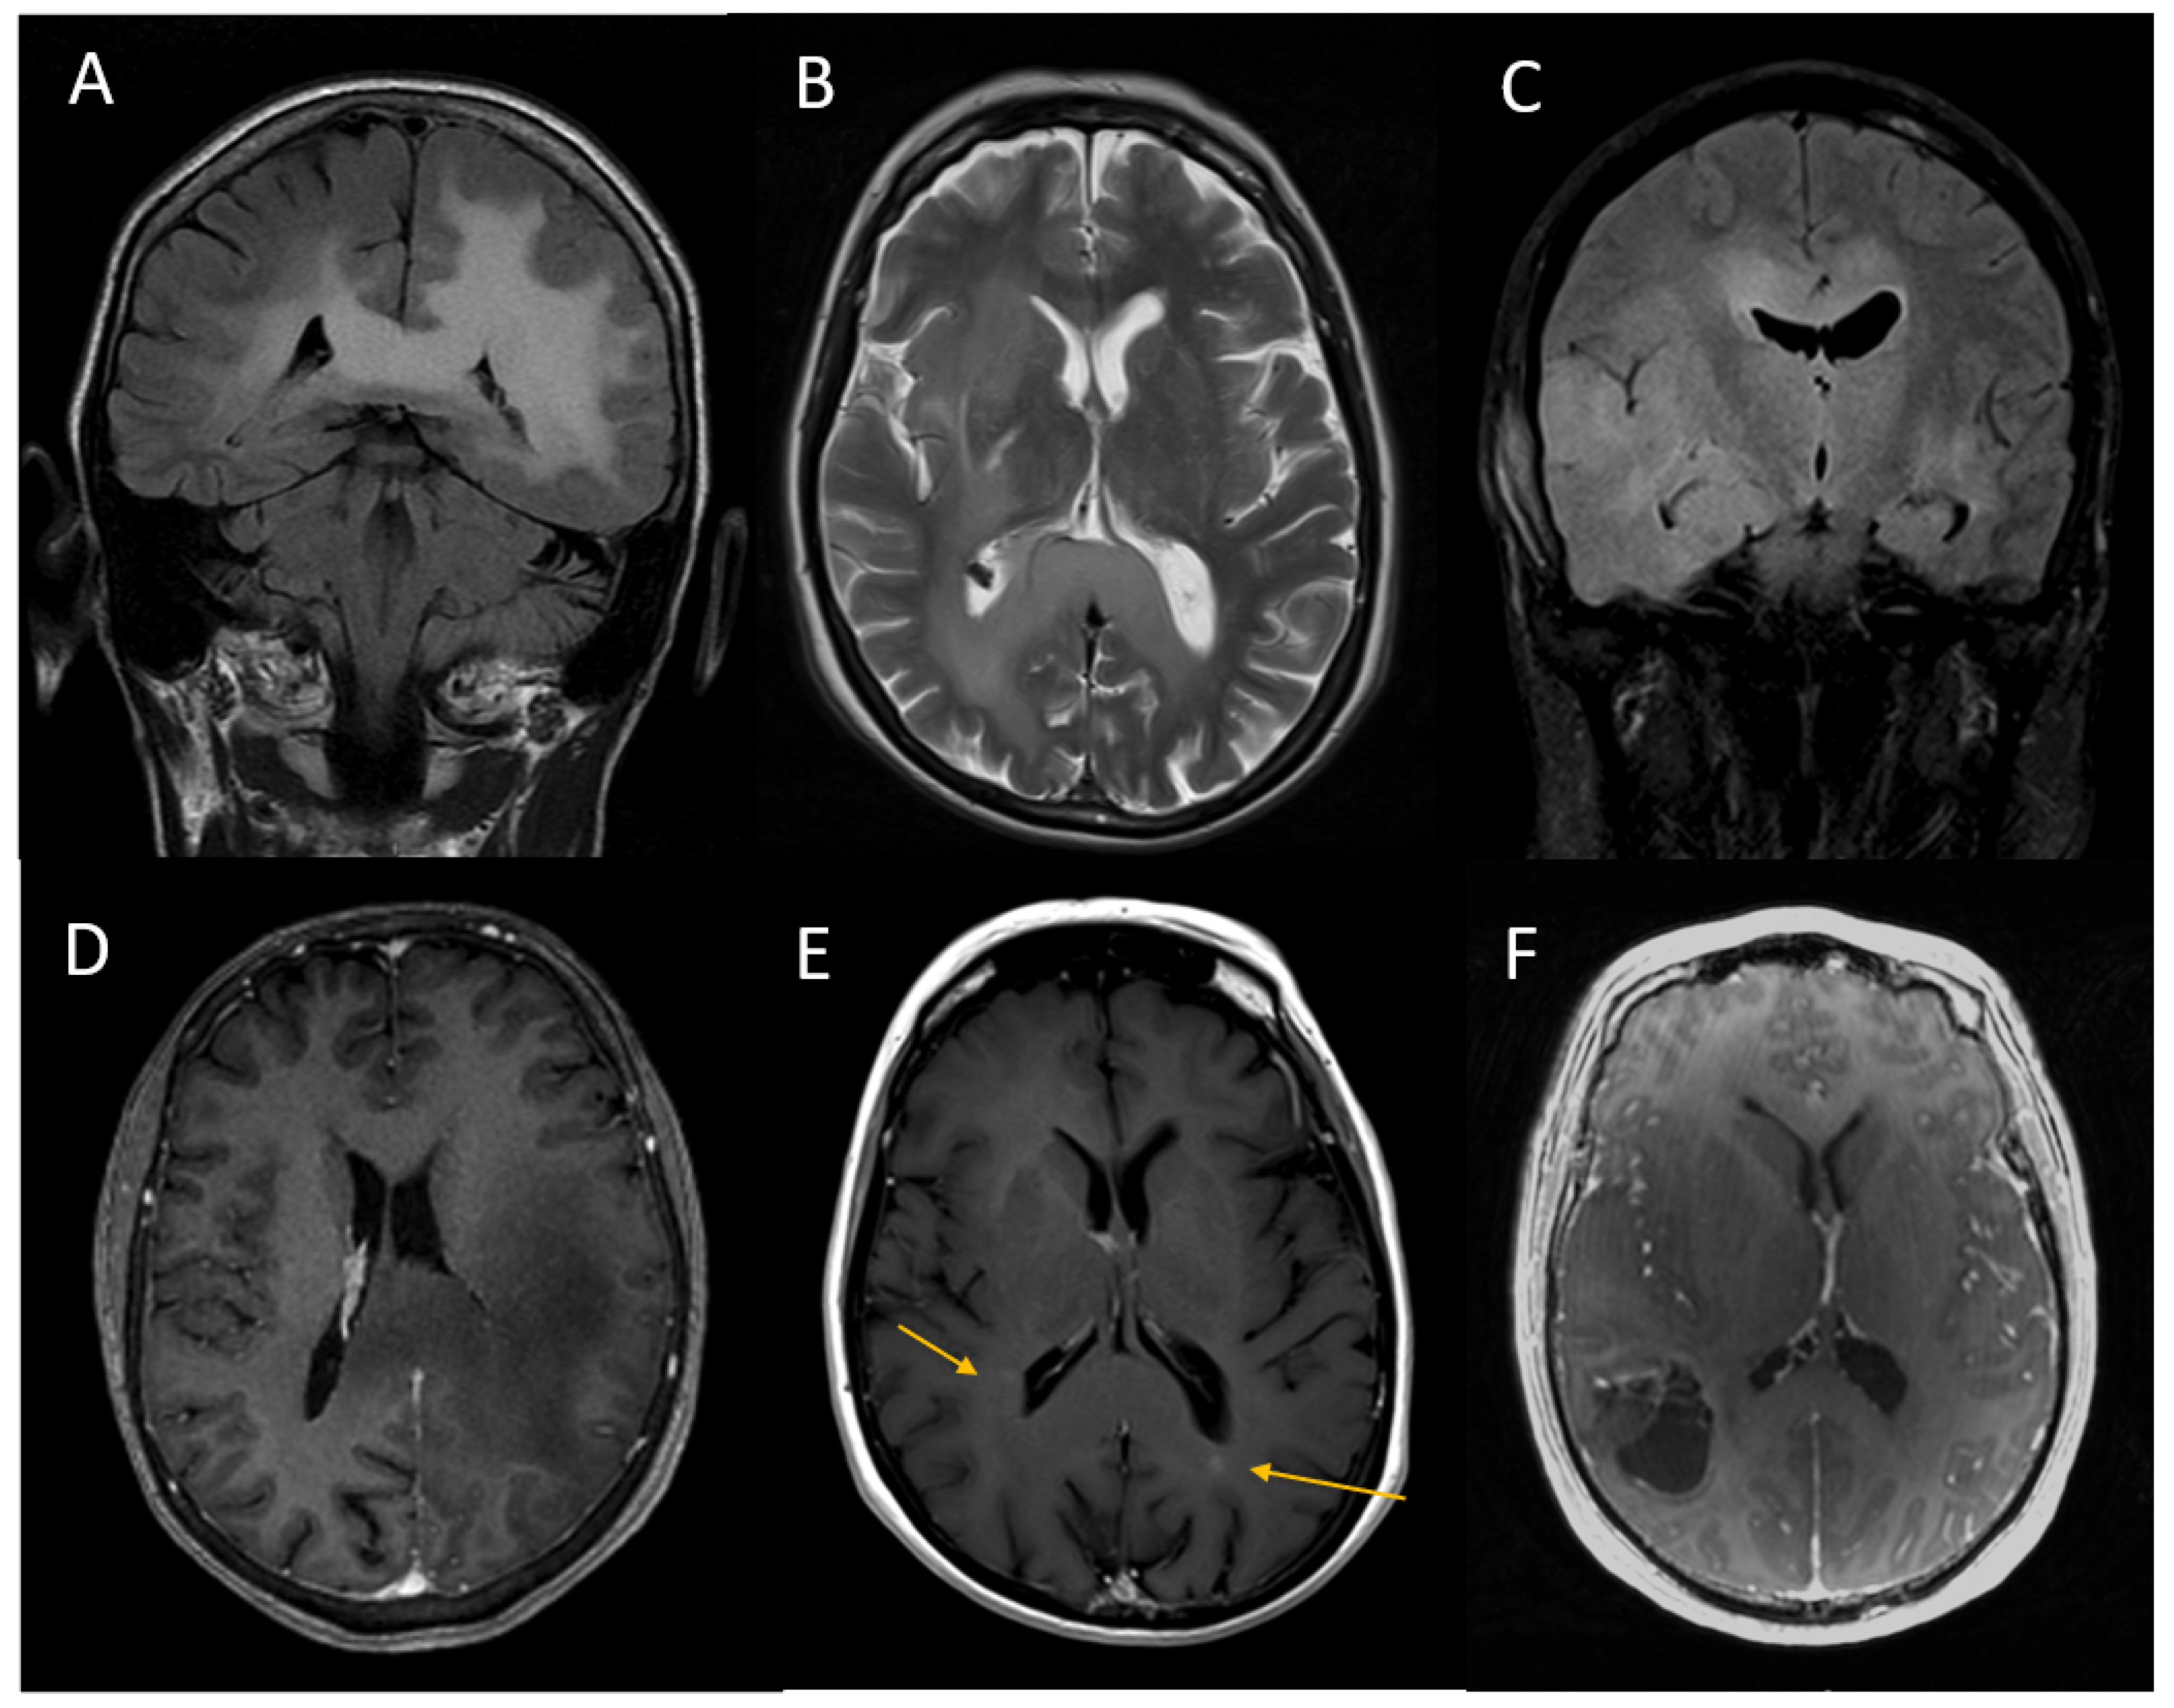

3.2. Imaging Tumour Characteristics